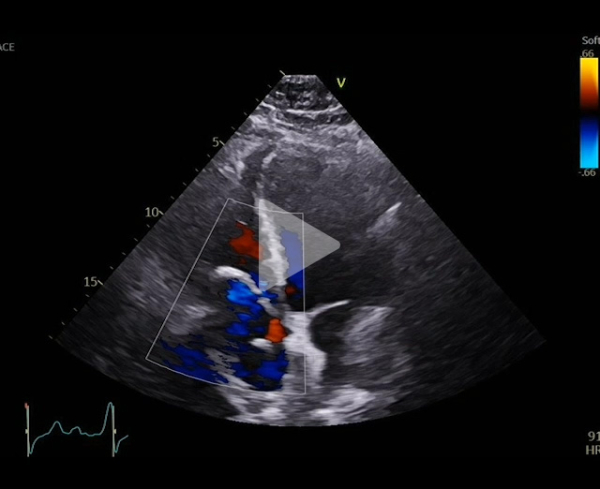

Vidéo 3

FEVG 30% , hypokinésie diffuse, pas de valvuloptahie aortique ni mitrale. VD non dilaté, normokinétique avec IT modérée. Prothèse en place avec passage de bulles résiduelles modéré. Sonde de DAI semblant extrêmement mobile.

Au cours du suivi, réapparition d’une dyspnée, se majorant progressivement jusqu’au stade 3 de la classification NHYA avec nouvelle ETT au mois d’aout 2025.